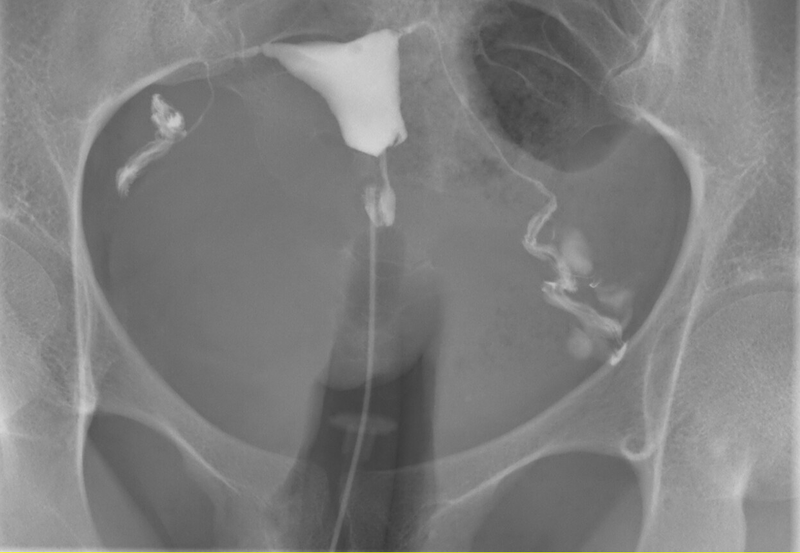

Chụp X-quang tử cung vòi trứng còn được gọi là chụp tử cung vòi trứng hay Hysterosalpingography, viết tắt là HSG. Với phương pháp này, bác sĩ sử dụng tia X-quang chiếu qua vùng tử cung, vòi trứng, buồng trứng 2 bên của người phụ nữ. Hình ảnh thu được nhằm quan sát xem ống dẫn trứng có bị tắc nghẽn không, hình dạng tử cung như thế nào hay có các dấu hiệu gì bất thường ở tử cung.

Thông qua những dữ liệu này, bác sĩ sẽ chẩn đoán được chính xác tình trạng tử cung vòi trứng, giúp tăng hiệu quả trong quá trình điều trị vô sinh hiếm muộn. Tùy vào cơ địa mỗi người mà kết quả chụp tử cung vòi trứng có thể khác nhau theo thời gian.

Nhờ vào kết quả chụp X-quang tử cung vòi trứng, bác sĩ có thể quan sát và chẩn đoán được: